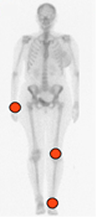

La forma difusa ataca la sinovial de las articulaciones y las bursas, siendo la articulación patelofemoral la mas afectada. (13). (Fig 48).

Fig 48. Distribución de la sinovitis villonodular pigmentaria.

La forma difusa es mas frecuente en la rodilla y la localizada en los dedos de las manos y los pies.